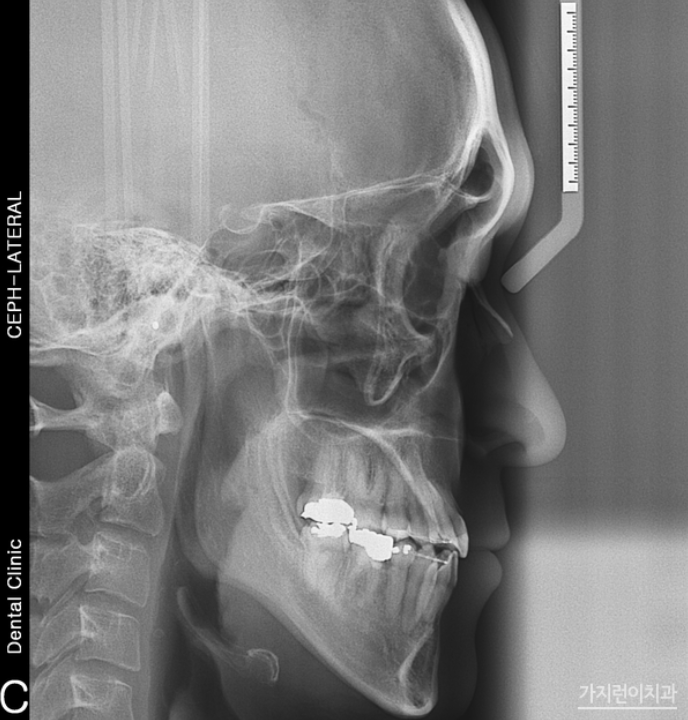

상단의 사진의 경우 주걱턱 케이스인데요. 아래턱이 유독 튀어나온 경우임에도 수술 없이 치아교정을 통해 개선한 경우입니다. 치료에 앞서 발치를 진행하는 것 만으로도 충분히 아래 턱을 집어넣을 수 있다고 판단했기 때문인데요. 결코 무리한 과정이 아닌 가능하다고 판단했기 때문에 진행했기 때문에 안정적으로 진행해볼 수 있었습니다. 효과적으로 치아를 후방이동 시키기 위해 미니 스크류를 식립한 후 교정용 고무줄을 연결했는데요. 주걱턱 양상과 덧니까지 함께 관찰이 되었다면 측면에서 관찰해도 정상교합으로 맞춰질 수 있도록 플랜을 구성해 니즈를 충족하고 있습니다. 특히 주걱턱, 덧니의 경우 이미지 변화가 큰 편인데요. 만족스런 결과를 보고 나도 해볼까? 라는 생각이 든다면 미리 상담 예약 후 방문해 도움 받아보시기 바랍니다.